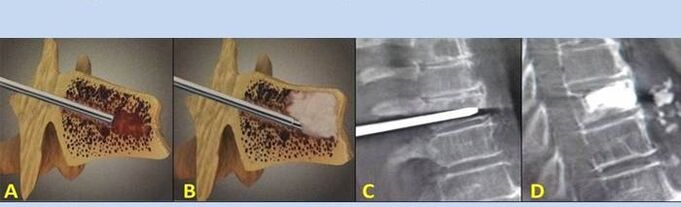

- Nucleoplasty- removal of the core of the intervertebral disc.The operation reduces the pressure on the nerve endings.

- Puncture vertebroplasty– the method of stabilizing the vertebrae.During the procedure, the doctor fills the spinal cavities with bone cement.